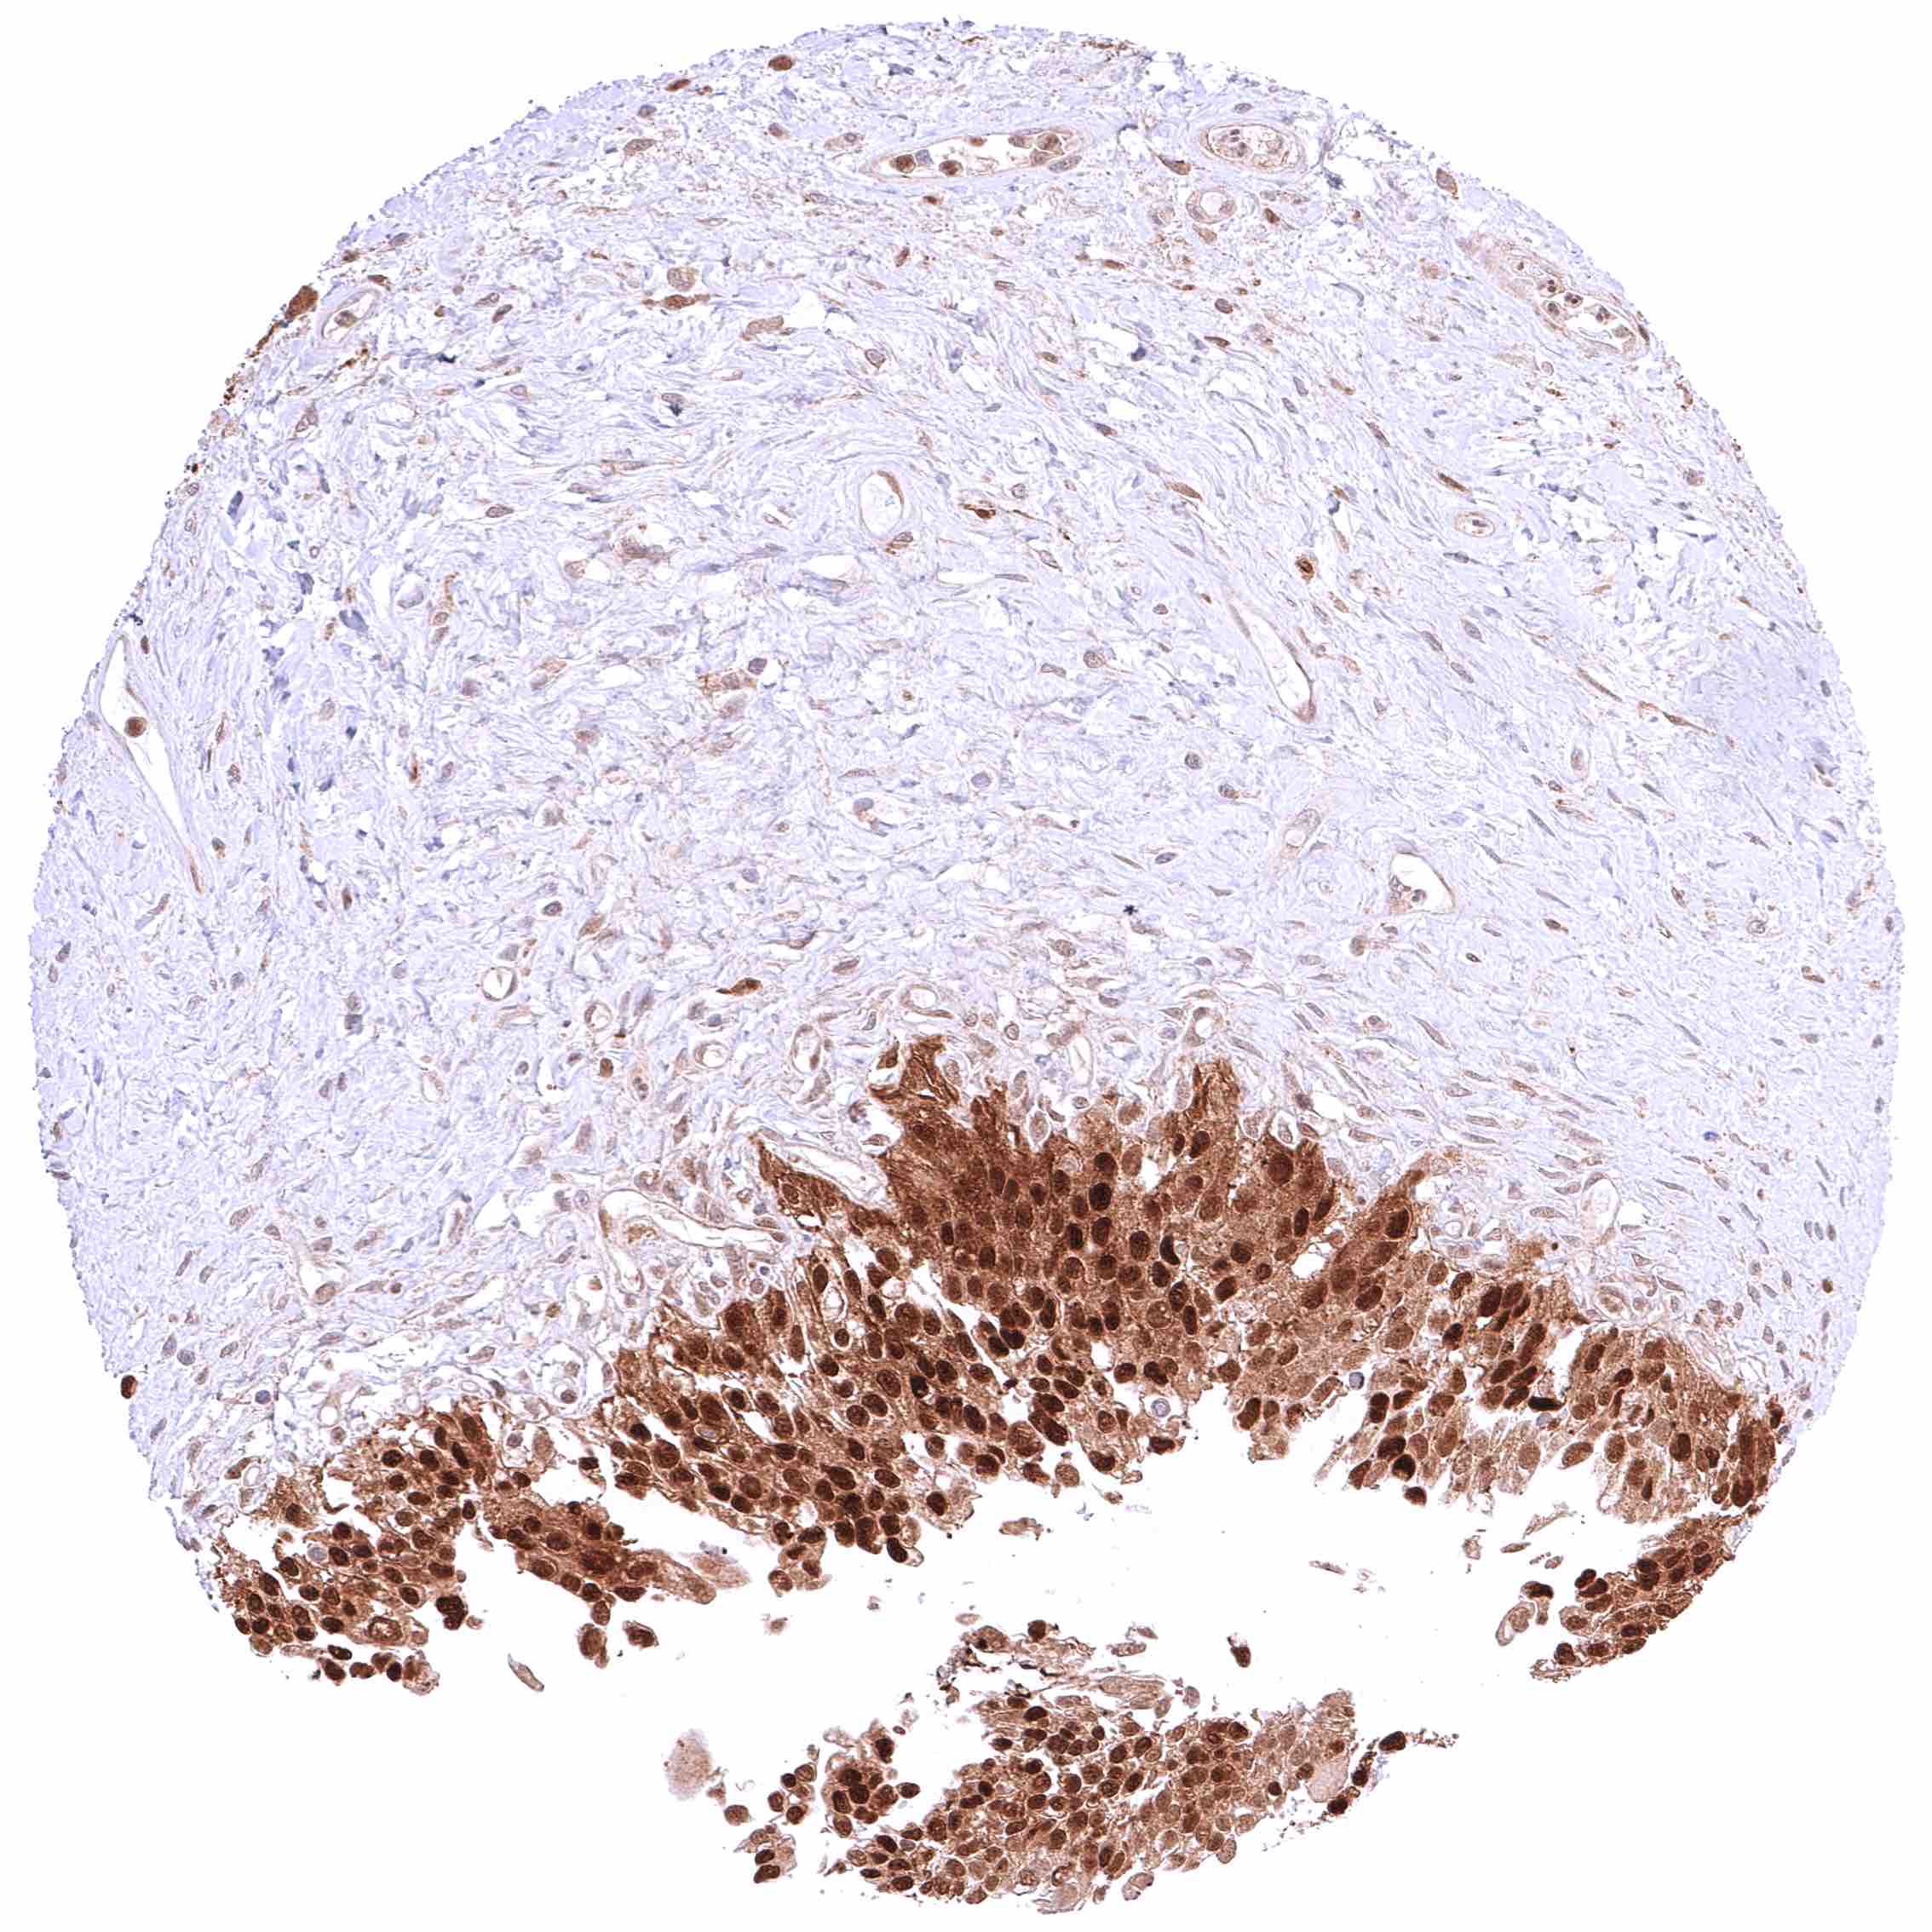

Uterus, ectocervix – Cytoplasmic and nuclear GSTP1 positivity of variable intensity of squamous epithelial cells. Staining intensity is highest in the basal and suprabasal cell layers and decreases towards the surface